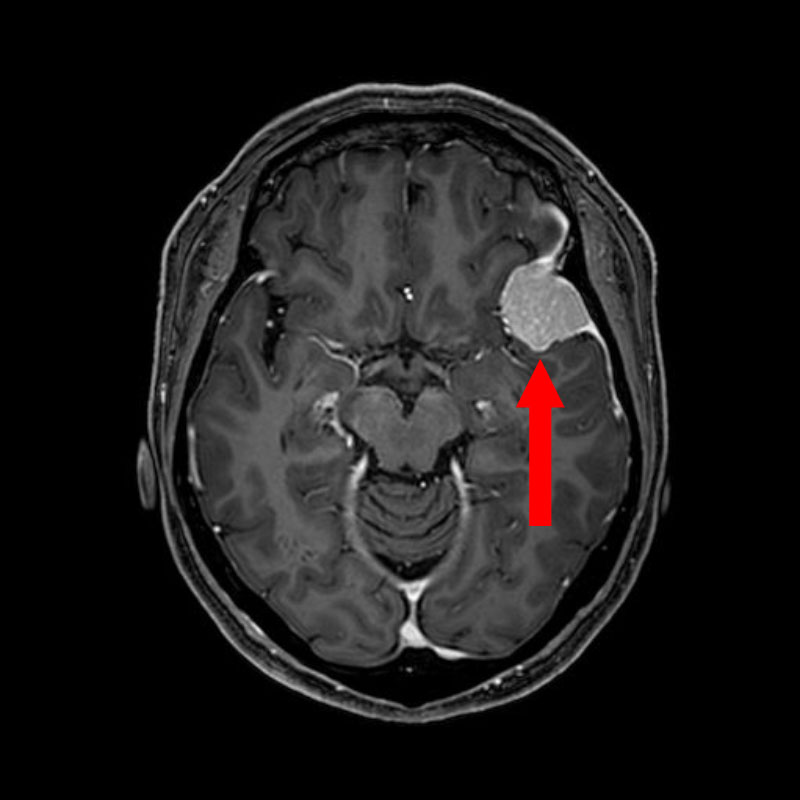

707

'25年12月

80代

髄膜腫

頭蓋内腫瘍摘出術

No.’25_109 手術前1

No.’25_109 手術前2